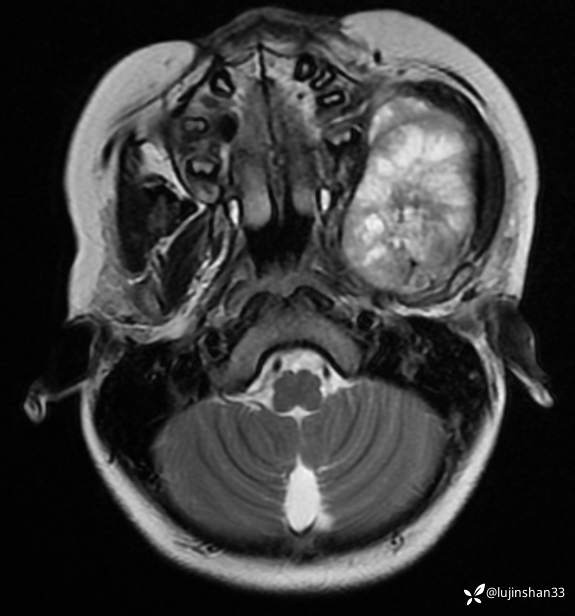

术后MRI:2022年2月考虑复发